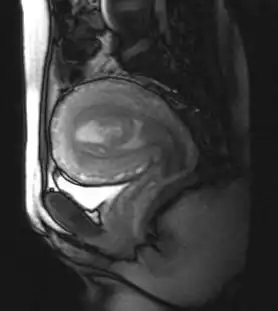

MRI showing retained products of conception in the first trimester[1]